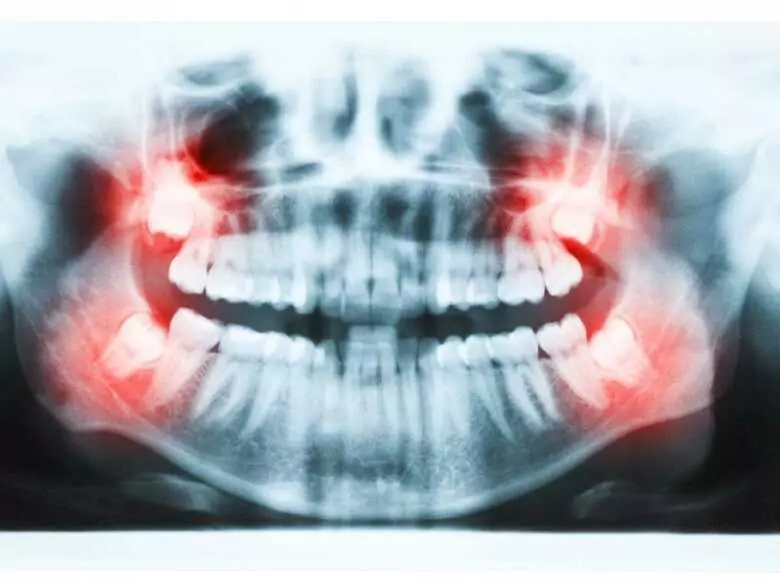

Wenn die Weisheitszähne durchbrechen, ist dies meist mit Schmerzen verbunden. Die Unannehmlichkeiten und das unangenehme Gefühl, wenn die Achter herauskommen, können von selbst abklingen, aber in manchen Fällen ist eine aktive Behandlung und das Eingreifen eines Spezialisten notwendig. Es gibt verschiedene Hausmittel, die das unangenehme Gefühl und die Beschwerden während des Durchbruchs der Achterzähne lindern können.